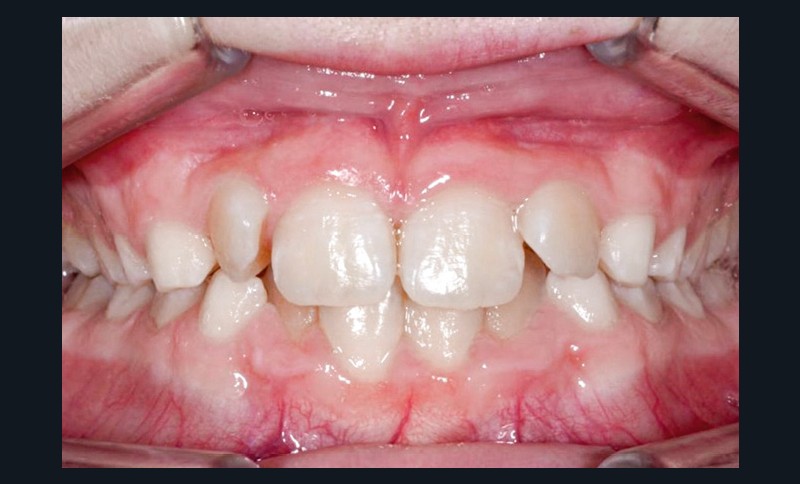

La patiente consulte à l’âge de 9 ans pour la malposition de ses incisives latérales maxillaires. Elle présente une occlusion de Classe I bilatérale sur un schéma normodivergent avec une dysharmonie dento-maxillaire en denture mixte. À l’arcade maxillaire, elle présente une endoalvéolie avec rotations mésiopalatines de 16 et 26.

Sur la radiographie panoramique, on observe une transposition des canines maxillaires en place d’incisives latérales, au contact des racines de 11 et 21.